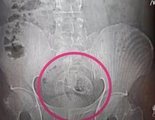

Intervenido de urgencia tras introducirse un pescado de 40 centímetros por el ano

El hombre acudió a Urgencias con un cuadro de dolor abdominal hasta que una radiografía reveló qué había sucedido.